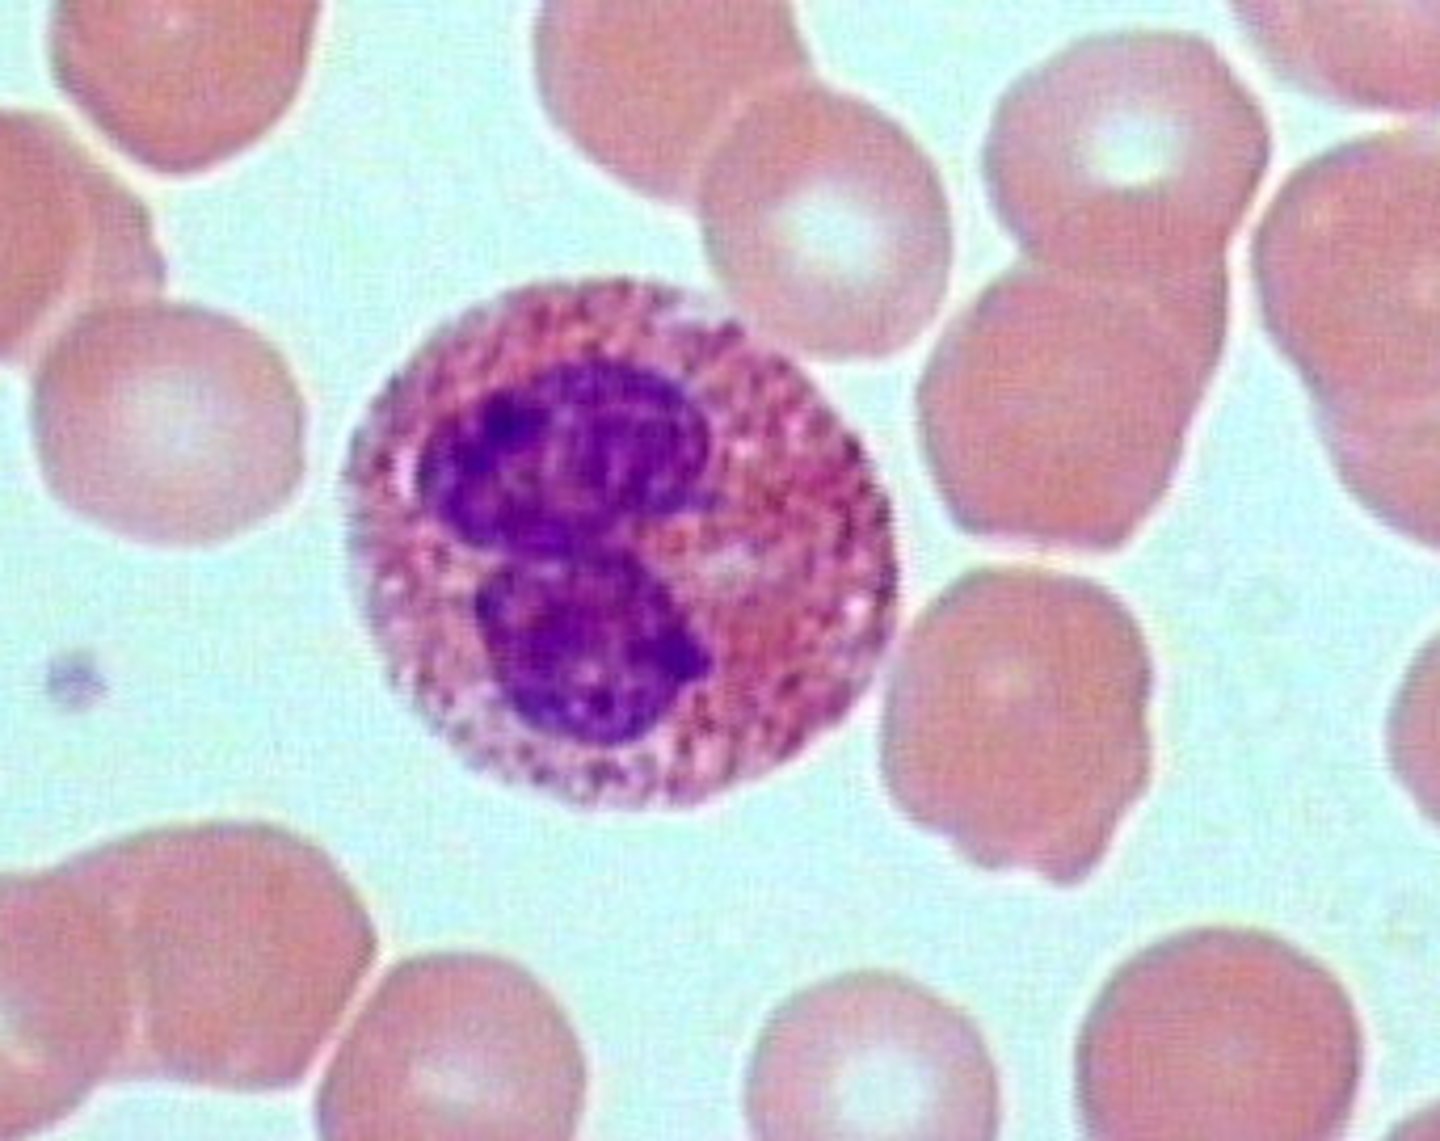

monocyte

MAMMAL

indented nucleus, basophilic cytoplasm